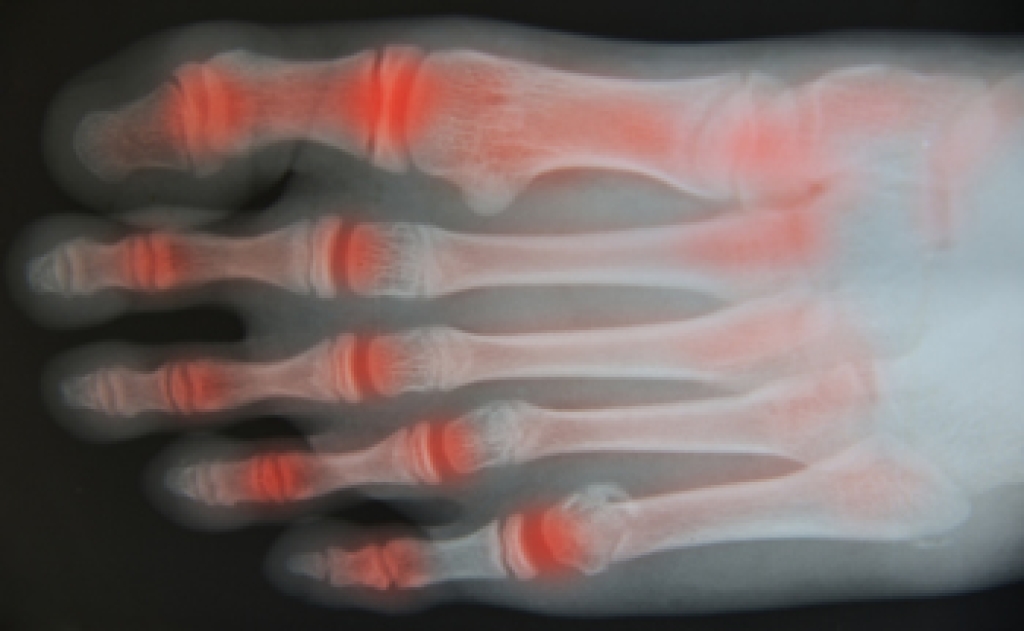

As we journey through life, our bodies undergo a multitude of changes, and our feet are no exception. The feet of the elderly have unique characteristics that reflect the wear and tear of a lifetime. One of the most noticeable features is the gradual flattening of the arches, causing a broader, flatter foot shape. This can result in a greater risk of instability and falls. Skin changes are also common, with thinning skin that is more susceptible to injury and slower healing. Additionally, years of weight-bearing can lead to conditions such as bunions, hammertoes, and arthritis, which may cause pain and reduced mobility. Toenails may thicken, and the risk of fungal infections or ingrown nails increases. Circulation issues, often linked to diabetes or other medical conditions, can further complicate matters. Despite these changes, elderly feet are resilient, and with proper care, they can continue to support a fulfilling, active life. Understanding the characteristics of elderly feet is crucial for maintaining overall health and well-being. If you would like information about proper foot care for elderly people, it is suggested that you contact a podiatrist who can provide you with the knowledge you are seeking.

Common Conditions

- Neuropathy – can reduce feeling in the feet and can hide many life-threatening medical conditions.

- Foot sores – amongst the older population can be serious before they are discovered. Some of the problematic conditions they may face are:

- Loss of circulation in legs & feet

Diabetes and poor circulation can cause general loss of sensitivity over the years, turning a simple cut into a serious issue.